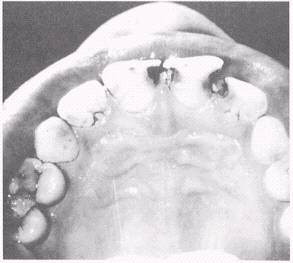

Man has suffered the effects of dental caries for centuries, and much study and research have been devoted to their causes and prevention. The disease is caused by a microbial process that starts on the surface of the teeth and leads to the breaking down of the enamel, dentin, and cementum, in some cases causing pulp exposure. This pathologic break that is produced on or in the tooth surface is called acarious lesion (fig. 5-4) or commonly called a cavity. The process that destroys the hard surfaces of the tooth is called decay.

Figure 5-4.\Carious lesions.